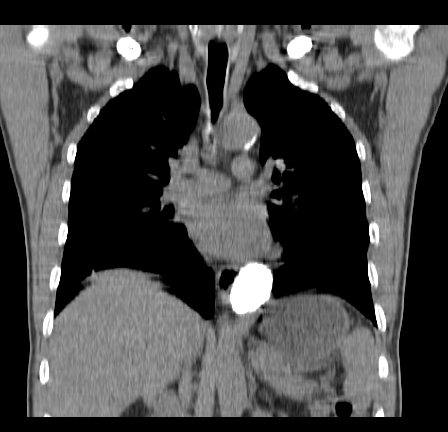

以下是引用影像孺子牛在2009-5-20 23:18:00的发言:[br]左侧后心膈角处类椭圆形钙化灶,最常见的是淋巴结钙化,但太大了不支持,其它如食管囊肿钙化、实性畸胆瘤等。何东西钙化真不好定。

以下是引用zbp537在2009-5-20 20:52:00的发言:[br]钙化灶,来源不好说。